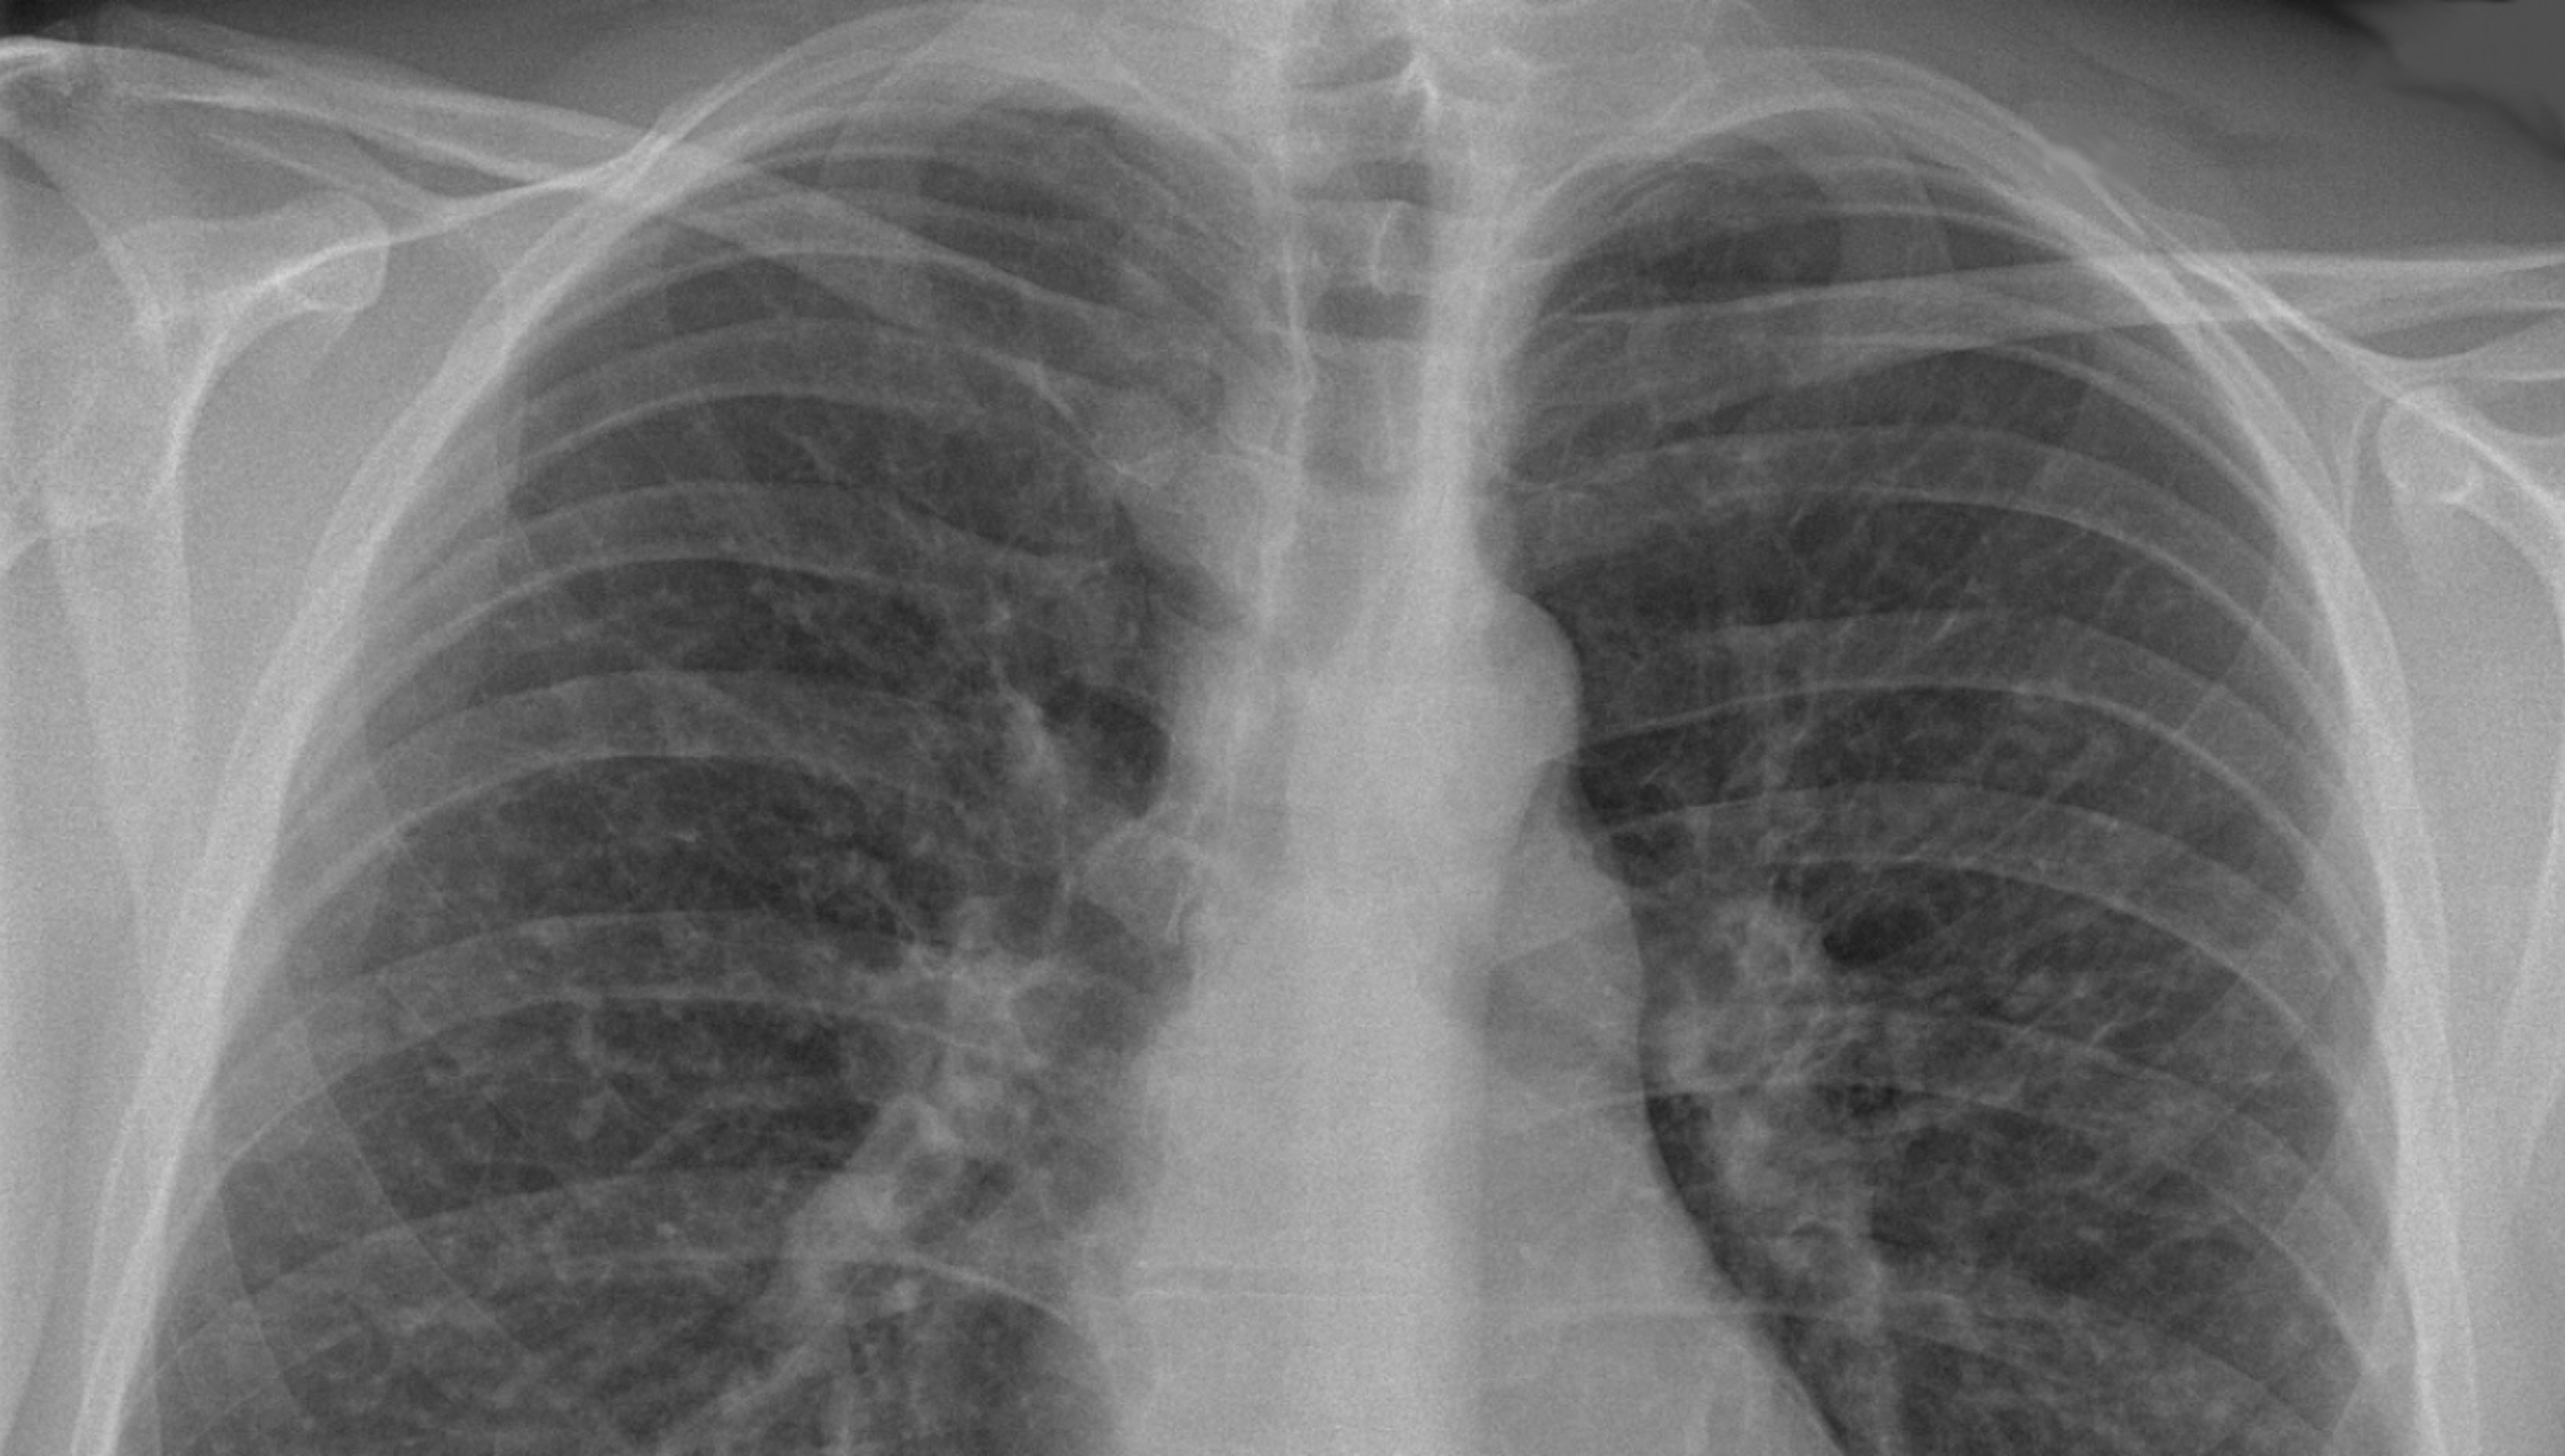

El cribado del cáncer de pulmón en los estudios mencionados se efectúa mediante una prueba de imagen, la tomografía computarizada de baja dosis de radiación (TCBD), en pacientes de alto riesgo. El estudio norteamericano NSLT ya había demostrado una reducción global de la mortalidad por cáncer de pulmón directamente atribuible al cribado de esta enfermedad. En Europa, los estudios científicos llevados a cabo posteriormente confirman este resultado e incluso lo mejoran, avalando la aplicación del cribado de cáncer de pulmón en población europea y, por tanto, española.